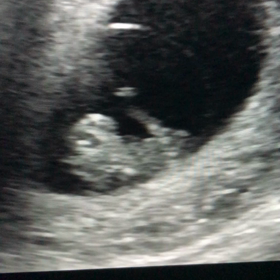

• エコー動画 8w4dの画像

エコー動画 8w4d

• エコー動画 9w1dの画像

エコー動画 9w1d

• エコー動画 9w6dの画像

エコー動画 9w6d